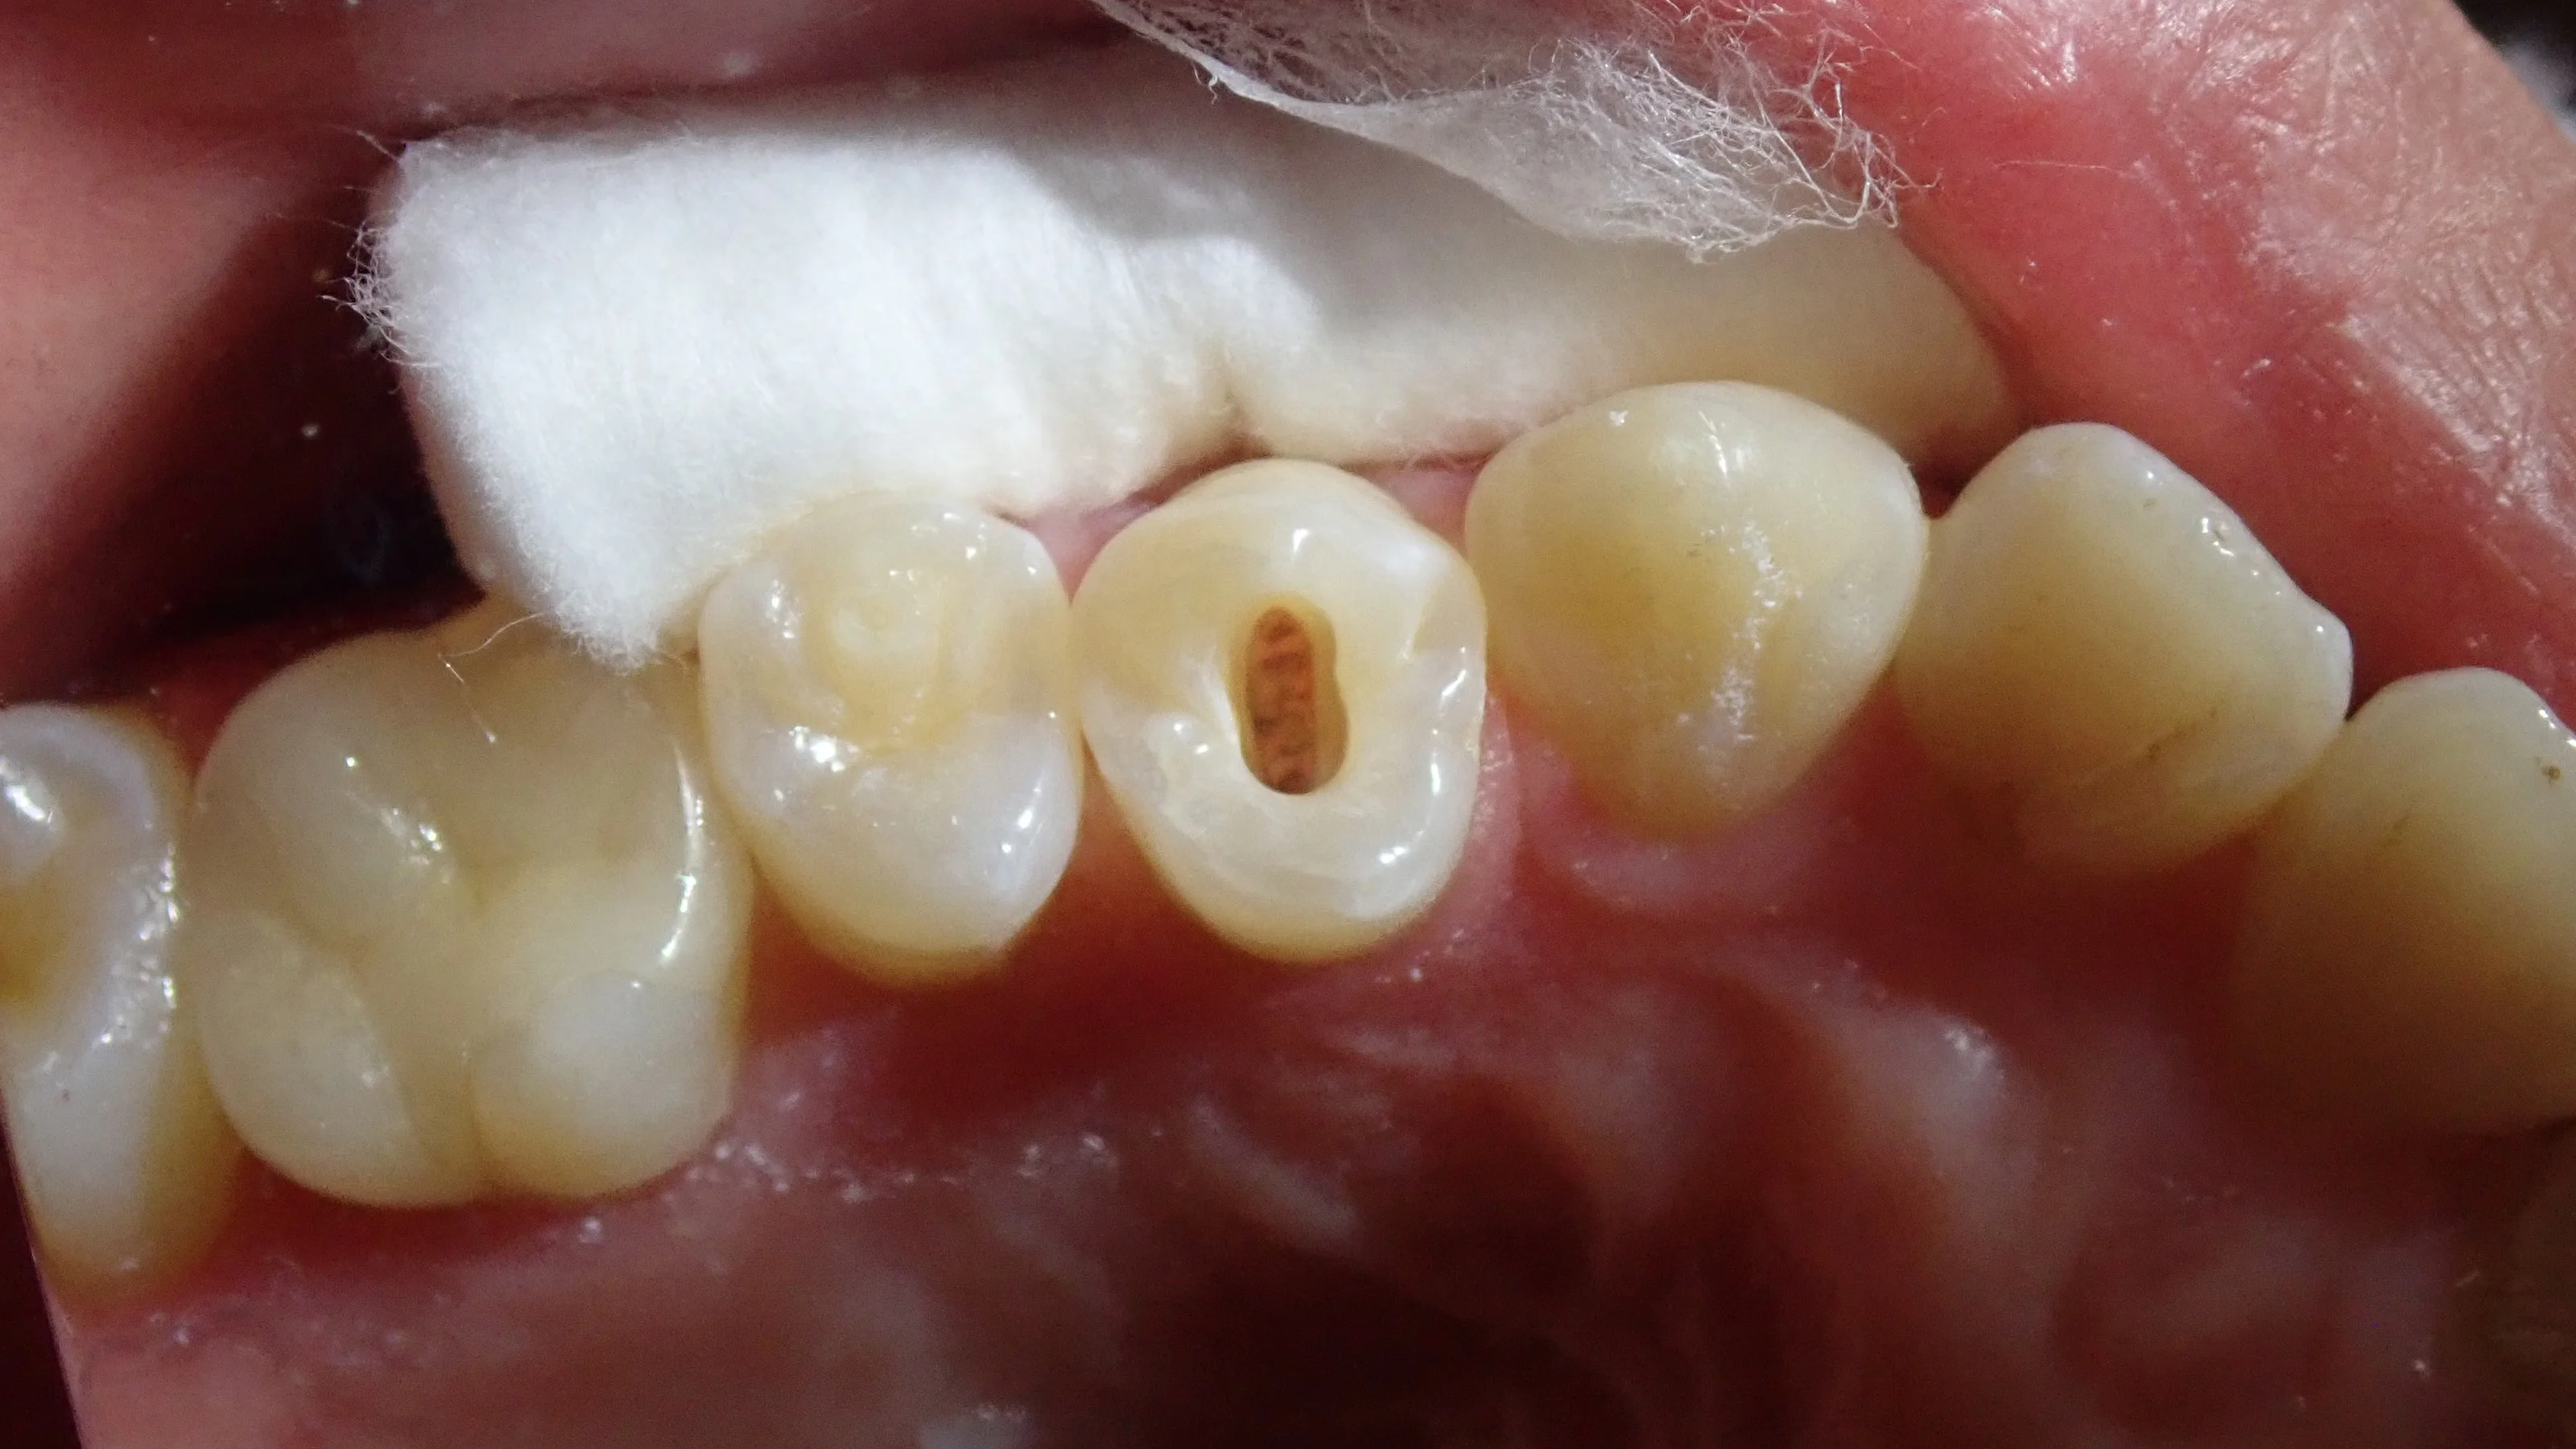

そして、お薬を詰め終わった写真がこちらです。

元々中心結節が折れることで感染を起こした状態でしたので、無駄に歯を削ったり、被せ物を入れたりする必要はありませんでした。

なので、こんな感じで、最小限の歯質削除を行って、神経の治療を行っていきました。